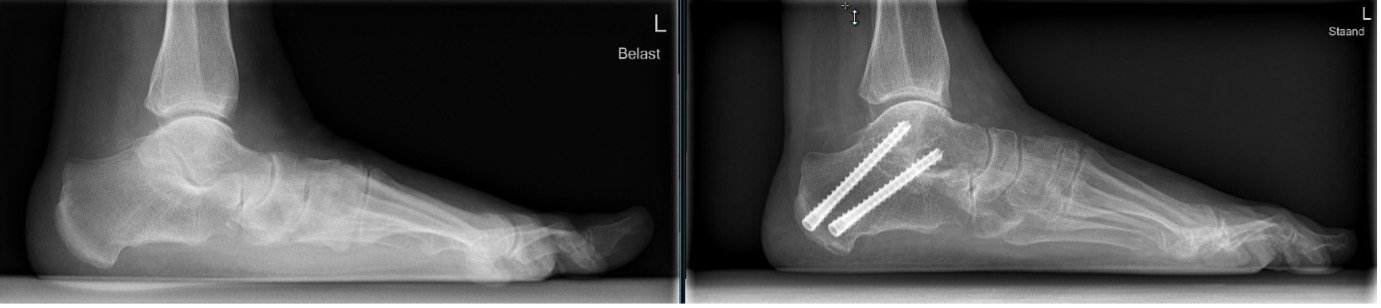

Op de foto's is duidelijke slijtage/artrose aanwezig van het bovenste spronggewricht

Het gewricht vastzetten door middel van een arthrodese

Een enkelarthrodese kan meestal via een arthroscopische (kijkoperatieve) techniek worden uitgevoerd. Het voordeel hiervan is dat er minder grote wonden ontstaan en minder kans op een wondinfectie is. Ook is het herstel na de ingreep sneller en gunstiger, en is er een grotere kans dat de arthrodese vastgroeit. Hiermee bedoelen we dat de twee botstukken aan elkaar groeien.

Tijdens de operatie wordt eerst het bot opgeruwd en daarna vastgezet met twee, soms drie, schroeven in een neutrale stand. Het voordeel van de arthrodese is dat de pijn verdwijnt en dat de enkel goed belastbaar is.